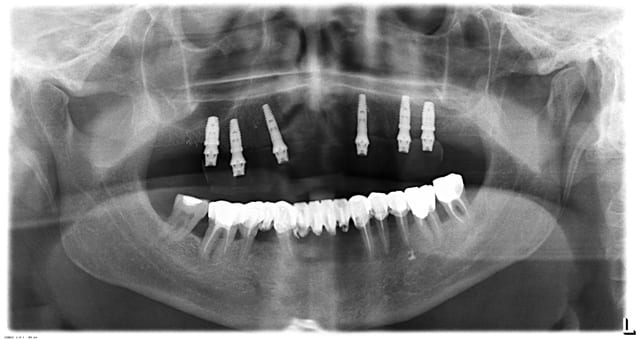

ci joint les panos du cas

j'envoie une ou 2 photos de la proth

des que j'ai 5 min

Pilo 01 qu2ktm - Eugenol

Pilo2 qjmjii - Eugenol

C'est lesquels que tu as perdu ?

De 16 a 23

je trouvais les axes et la répartition êtes forcés plutôt bonne